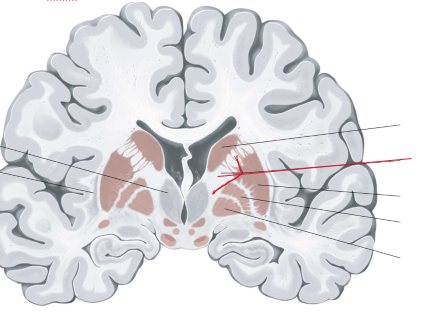

nucleus caudatus

putamen

globus pallidus

capsula interna (corona radiata)

capsula externa

capsula extrema

hippocampus

amygdala

fornix

laterale ventrikels (I en II)

septum pellucidum